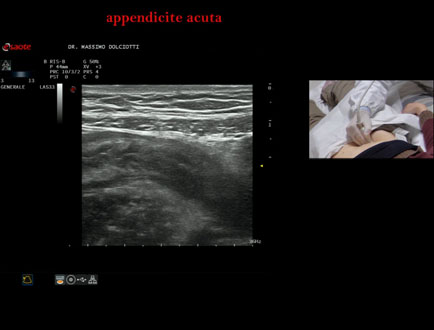

Data inserimento: 15/01/2026

Ecografia del: 07/01/2025

Strumento: Esaote MyLab Eight

Sonda: Lineare Multifrequenza 3-13 MHz

Età Paziente: F 39 anni

Motivazione dell'esame: dolori addominali epiastrici da 2 gg, anche notturni, non nausea, non vomito, non diarrea, non febbre, diuresi normale, nicturia saltuariamente.

Commento all'esame: le immagini ed il video documentano, in sede ileo-cecale, appendice di spessore aumentato (11 mm - V.N. inferiore a 6 mm). Gli elementi ecografici segnalati orientano per appendicite acuta.

Conclusioni: appendicite acuta (acute appendicitis).

In collaborazione: Dr.ssa Marica Manfredi - Ancona, Dr. Ilir Qose - Ancona

Presentazione: Dr. Massimo Dolciotti - Ancona

Elaborazione digitale: Andrea Dini - Ancona